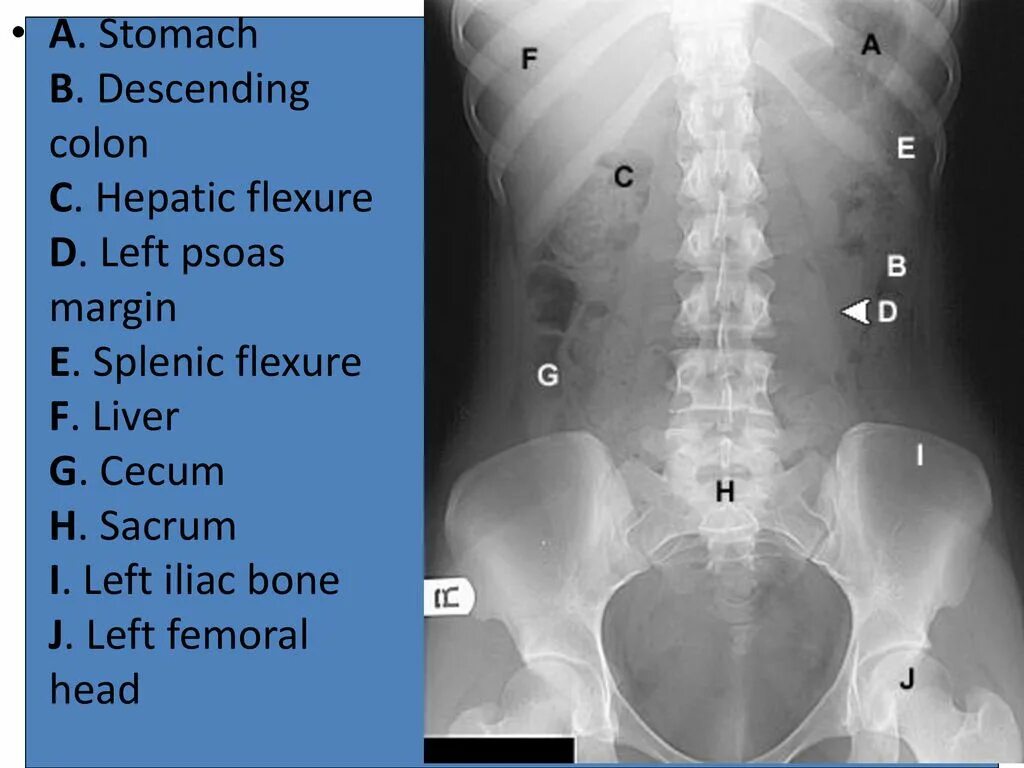

Псоас симптом